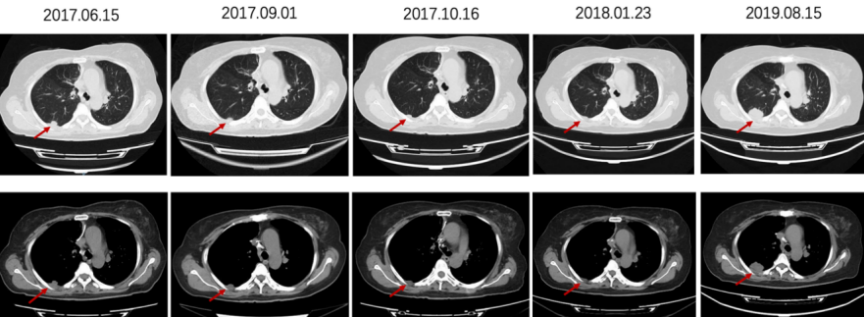

2017-6-15 复查胸部CT:右下肺胸膜下软组织密度结节,考虑肿瘤复发。2017-7至2017-10 贝伐珠单抗+FOLFIRI治疗8周期,后卡培他滨+贝伐珠单抗维持治疗至2019-8,并口服中药治疗。(PFS 25个月)

图3 右下肺胸膜下结节随访变化